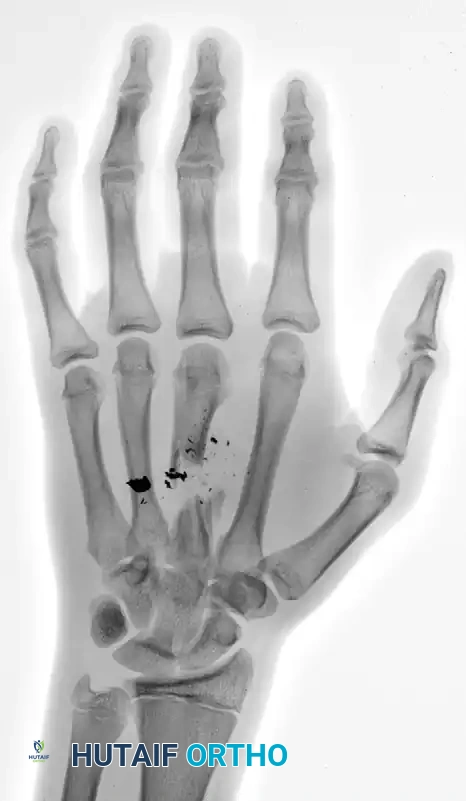

FIGURE 67-4 A and B: Comminuted middle finger metacarpal shaft fracture with intercalary bone loss from a self-inflicted handgun injury in a 17-year-old boy.

Figure 67-4 A: Anteroposterior (AP) radiograph demonstrating a highly comminuted fracture of the third metacarpal with significant segmental bone loss and retained ballistic fragments.